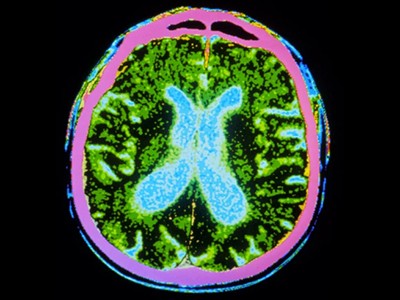

圖1:帕金森病的干細(xì)胞療法。

帕金森病是由于大腦中釋放多巴胺(多巴胺能)神經(jīng)元逐漸喪失所致。Sawamoto 等人1和 Tabar 等人2進(jìn)行了一項(xiàng)基于干細(xì)胞治療的臨床試驗(yàn)。兩個(gè)團(tuán)隊(duì)都使用了臨床級(jí)多能干細(xì)胞來(lái)補(bǔ)充多巴胺能神經(jīng)元,這種細(xì)胞可以無(wú)限分裂并分化為任何細(xì)胞類型。Sawamoto等人使用了源自健康成年捐贈(zèng)者細(xì)胞的誘導(dǎo)多能干細(xì)胞系,而Tabar等人使用了源自早期胚胎的人類胚胎干細(xì)胞系。干細(xì)胞經(jīng)過(guò)培養(yǎng),形成多巴胺能神經(jīng)元祖細(xì)胞。這些細(xì)胞被移植到稱為殼核的大腦區(qū)域,殼核與尾狀核一起形成紋狀體。紋狀體與黑質(zhì)相連,而黑質(zhì)是多巴胺能神經(jīng)元損失最為嚴(yán)重的部位。早期(I/II期)臨床試驗(yàn)主要證實(shí)了該療法的安全性,同時(shí)也表明其在改善癥狀方面具有一定有效性。